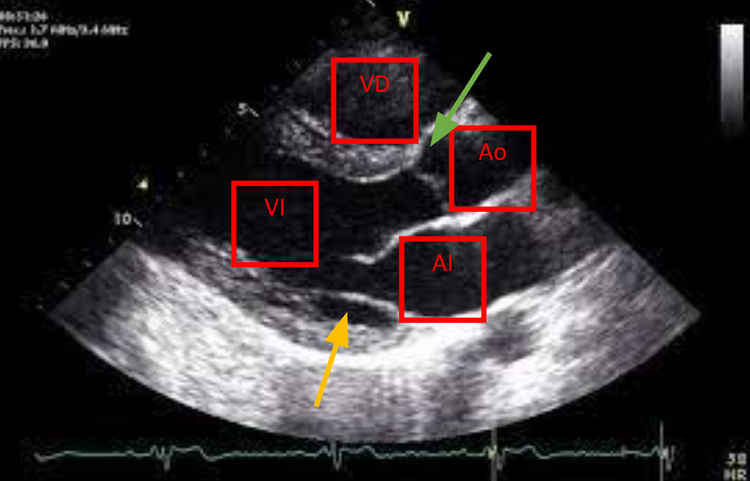

#12. Así es un ecocardiograma. Cómo ver tu corazón.

Vale. Te han pedido un ecocardiograma y no sabes qué pasa.  O qué se ve.  ¿Para qué sirve eso? ¿Hace